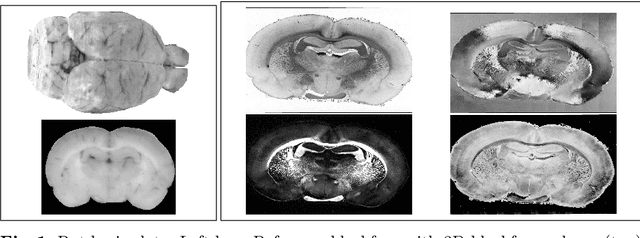

Abstract:3D reconstruction of the fiber connectivity of the rat brain at microscopic scale enables gaining detailed insight about the complex structural organization of the brain. We introduce a new method for registration and 3D reconstruction of high- and ultra-high resolution (64 $\mu$m and 1.3 $\mu$m pixel size) histological images of a Wistar rat brain acquired by 3D polarized light imaging (3D-PLI). Our method exploits multi-scale and multi-modal 3D-PLI data up to cellular resolution. We propose a new feature transform-based similarity measure and a weighted regularization scheme for accurate and robust non-rigid registration. To transform the 1.3 $\mu$m ultra-high resolution data to the reference blockface images a feature-based registration method followed by a non-rigid registration is proposed. Our approach has been successfully applied to 278 histological sections of a rat brain and the performance has been quantitatively evaluated using manually placed landmarks by an expert.